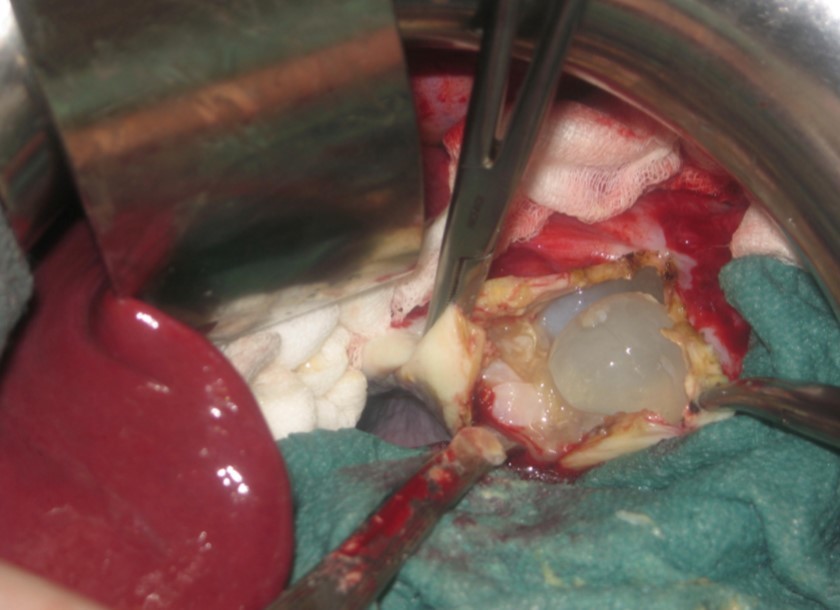

A 17-year-old young man admitted to our department with the complaint of abdominal pain localized in the left upper quadrant for the last 3 months. His physical examination revealed a splenomegaly. Immunoblot assay for Echinococcus was positive. His laboratory tests showed normal results of the serum and urine examinations, No eosinophilia was found. Chest X-ray revealed no pathological signs. An abdominal ultrasonography showed a 20 cm multivesicular cystic mass of spleen (figure 1). Contrast enhanced CT scans detected a huge single 20×16×18cm cystic mass located in the spleen. It had well-defined borders and contained multiple, round, daughter cysts in the periphery of the lesion with calcification (Figure 2, Figure 3, Figure 4). The patient underwent a laparotomy. A large splenic cystic mass was identified, attached to diaphragm, and tail of the pancreas (figure 5). The abdomen was packed with 10% hypertonic saline soaked pads in order to protect peritoneal soilage. A partial cystectomy without splenectomy was performed. Histologic examination of the specimen resection showed an echinococcal organism residing within the hydatid cyst . The patient was discharged after 4 postoperative days. 600 mg per a day of Albendazole therapy was instaured postoperatively and continued for 6 months. Two years after surgery the patient is well with disease free.

Figure 5.Intraoperative view showing multivesicular spleen hydatid cyst.